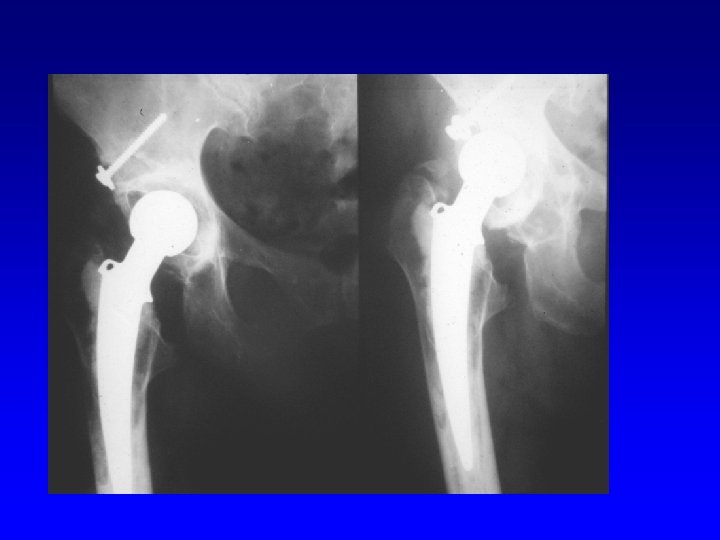

Fixation in the bone Types of THA Cemented Hybrid Uncemented

Primary THA Polyethylene cup Head Neck Stem

Revision THA

Femoral component • High polished surface for cementing fixation • Porous surface for cementless fixation Cemented Cementless